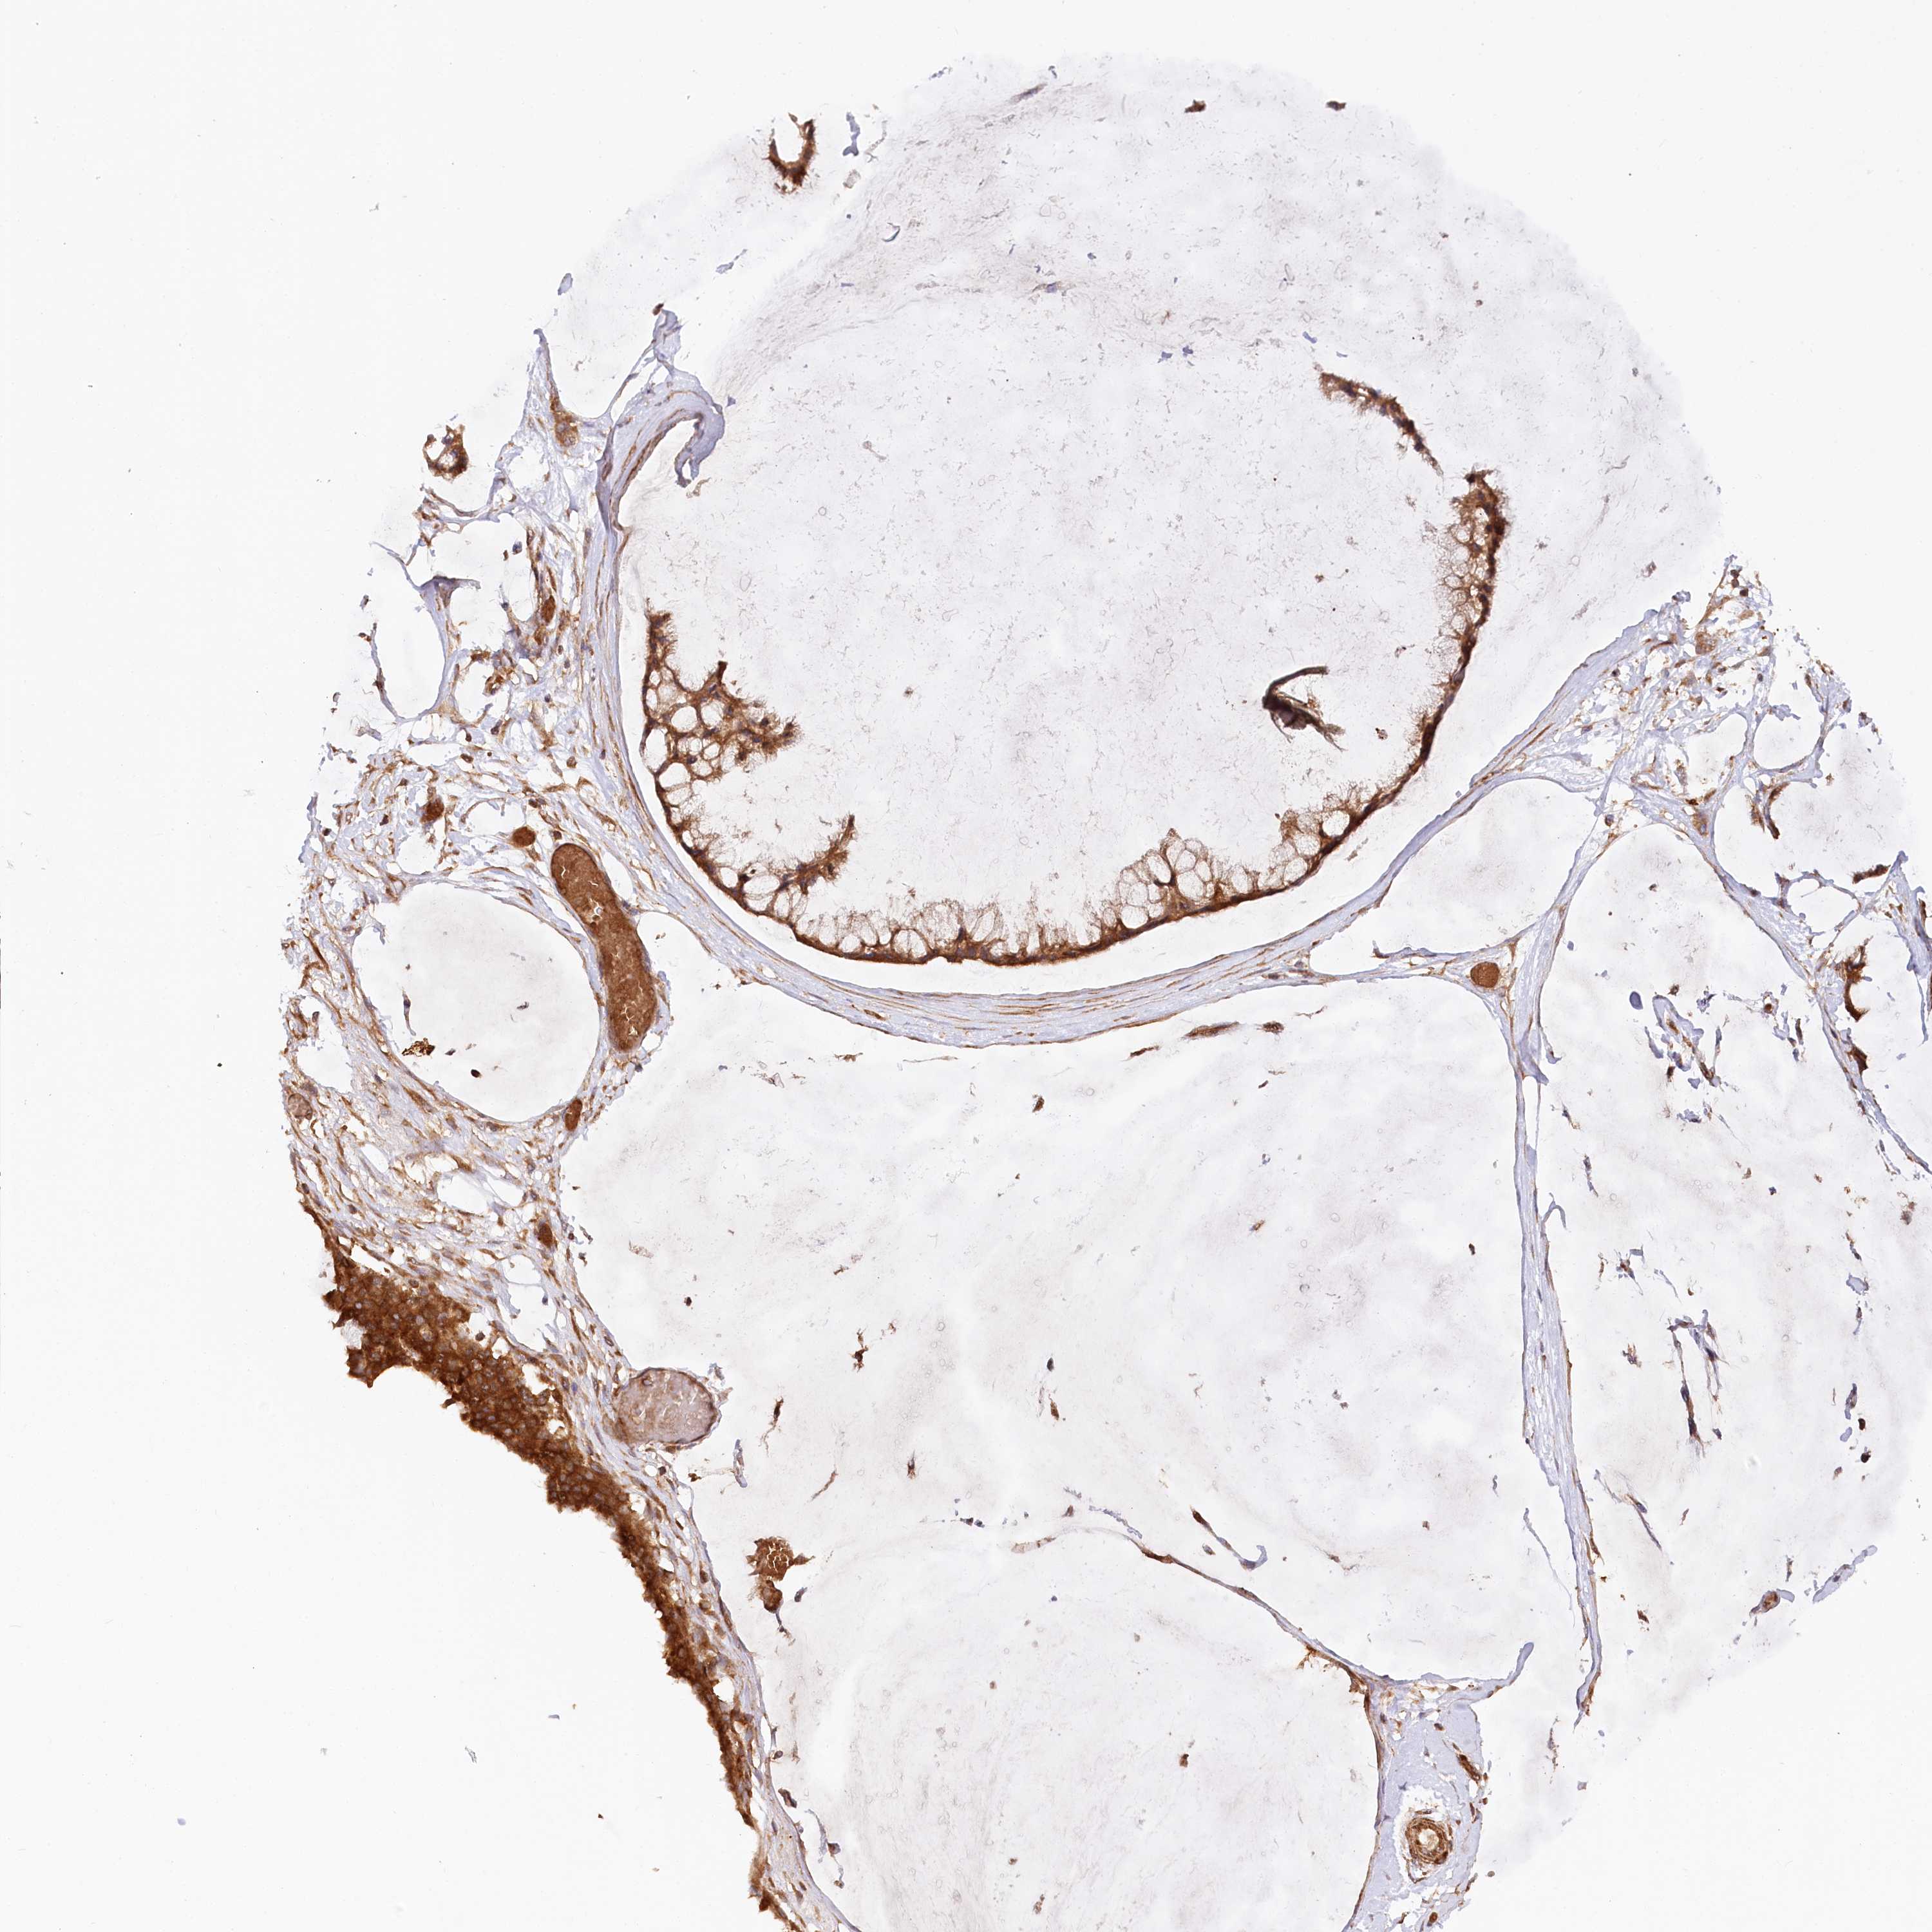

OVARIAN CANCER - Protein expressioni

A mouse-over function shows sample information and annotation data. Click on an image to view it in a full screen mode. Samples can be filtered based on level of antibody staining by selecting one or several of the following categories: high, medium, low and not detected. The assay and annotation is described here.

Note that samples used for immunohistochemistry by the Human Protein Atlas do not correspond to samples in the TCGA dataset.

Antibody stainingi

Antibody staining in the annotated cell types in the current human tissue is reported as not detected, low, medium, or high, based on conventional immunohistochemistry profiling in selected tissues. This score is based on the combination of the staining intensity and fraction of stained cells.

Each image is clickable and will lead to virtual microscopy that enables deeper exploration of all samples and also displays staining intensity scores, fraction scores and subcellular localization as well as patient and tissue information for each sample.

Antibody HPA035945

Antibody HPA056766

Antibody CAB037212

Staining

High

Medium

Low

Not detected

Cystadenocarcinoma, serous, NOS

Carcinoma, endometroid

Cystadenocarcinoma, mucinous, NOS

Carcinoma, NOS